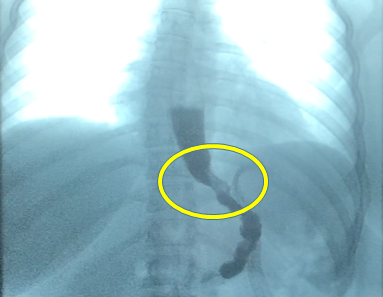

We have had clinically good results with the proximal gastric plication procedures we performed over the years to correct GERD in patients with different bariatric procedures including SG.3 The internal anti-reflux valve can be seen clearly in the X-ray and endoscopic studies we have performed after the surgery and has been found to persist in patients operated on more than five years after the original procedure (Figure 4).

Figure 4 A detailed photo of the internal anti-reflux gastric valve constructed with the proximal gastric plication.